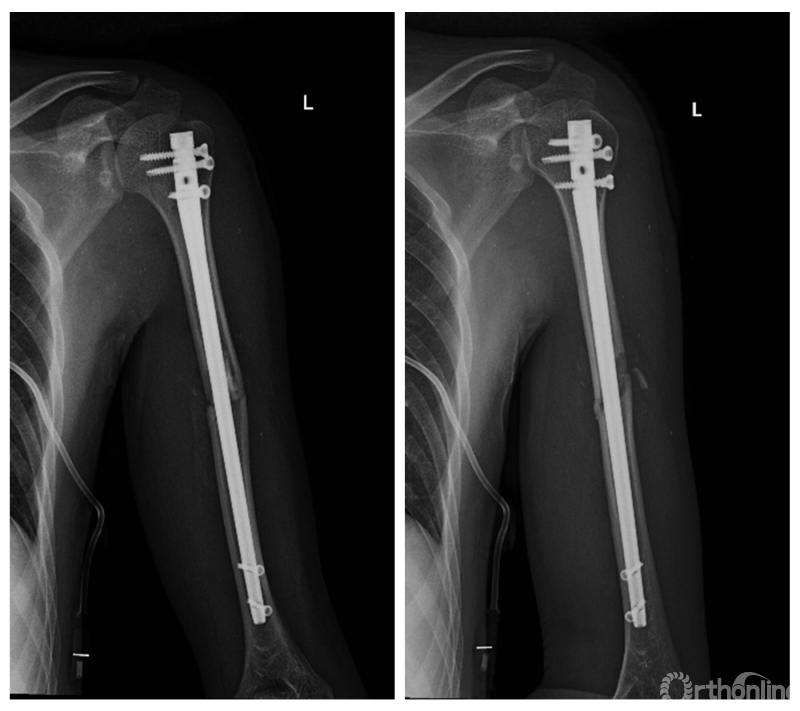

术后X线片

本次手术在术前利用“临床影像工作站”读取患者术前的CT影像数据,运用人工智能算法对骨折部位进行精准分割和重建,高效实施术前规划,术中利用光学导航系统精确制导,实现肱骨干骨折全息可视化复位、髓内钉精准定位。整台手术共耗时45 分钟,完全省去传统手术中采用C形臂透视辅助复位和置钉的过程。术后X线显示骨折端获得解剖复位,术后肢体活动良好。